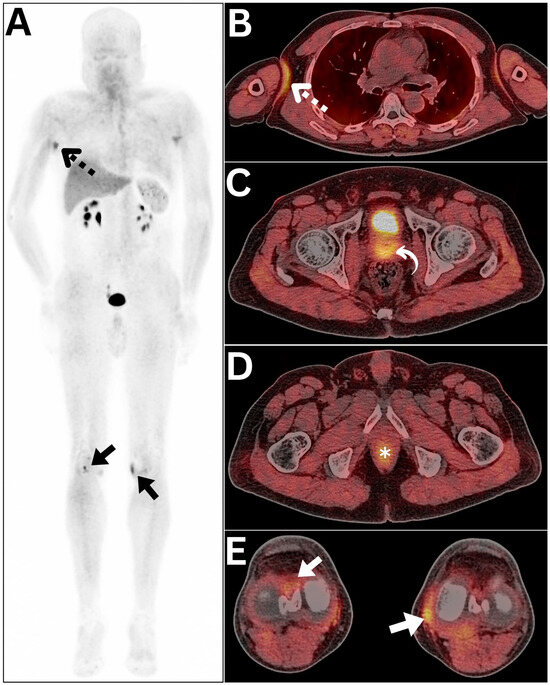

| 2 | Detection of primary lung lesion otherwise not depicted through FDG PET/CT molecular imaging | 18F-FDG PET/CT | Upscaled |

| 1 | Detection of primary medullary thyroid cancer and metastatic lesions otherwise not radiotracer-avid on 68Ga-DOTATOC imaging | 68Ga-DOTATOC PET/CT | Upscaled |

| 1 | Detection of small metastatic lymph nodes and hepatic lesions in a patient with high thyrocalcitonin levels but negative CT and ultrasound | CT and neck Ultrasound | Upscaled |